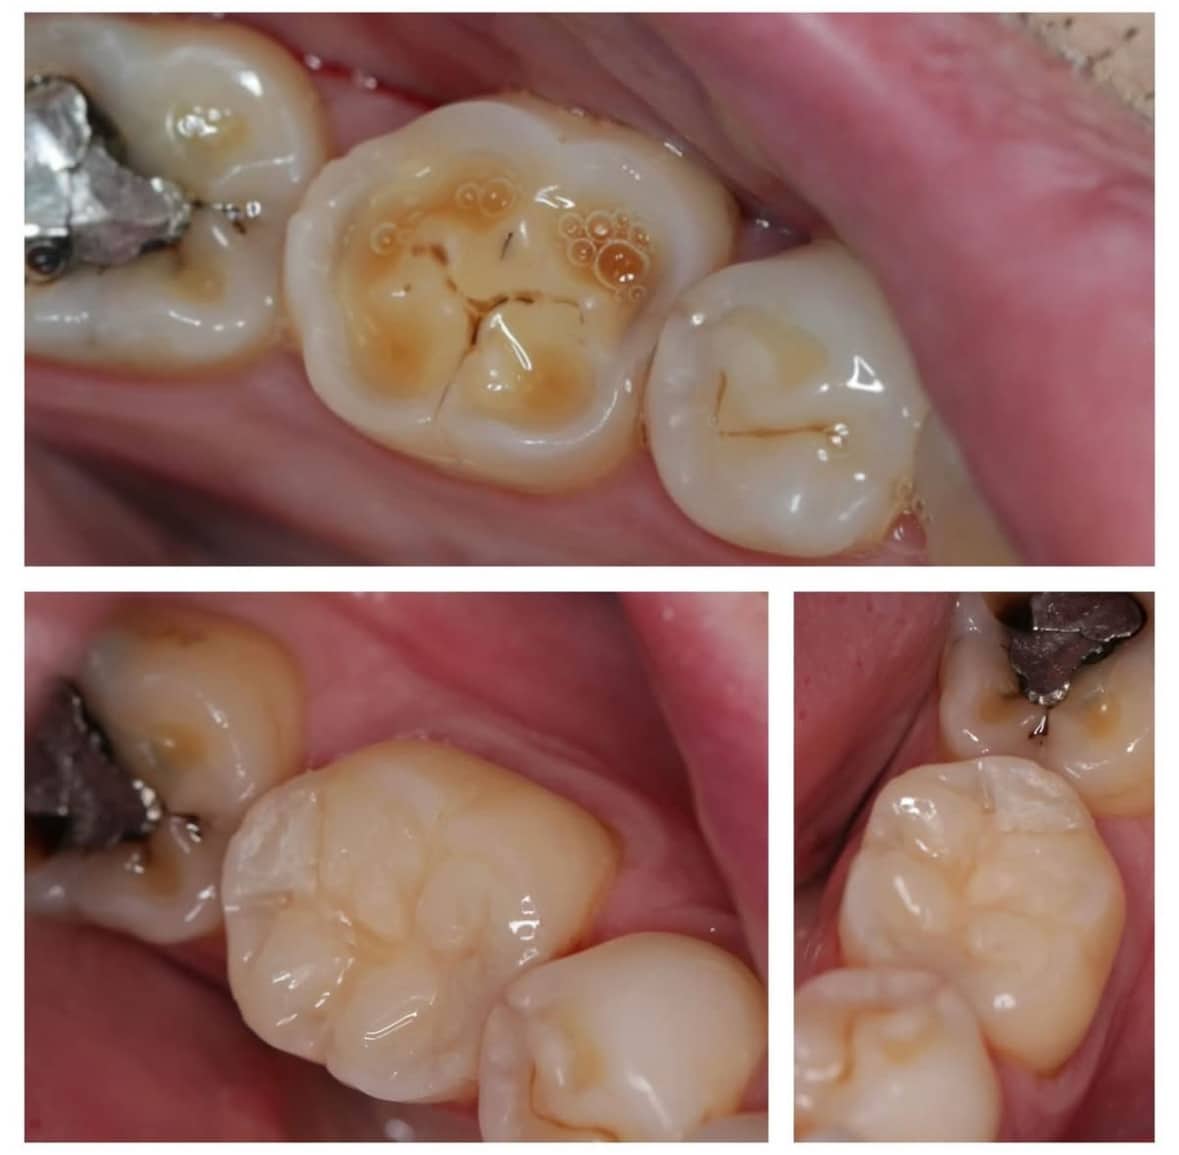

Esteetiline hambaravi, restauratiivne hambaravi, suukirurgia